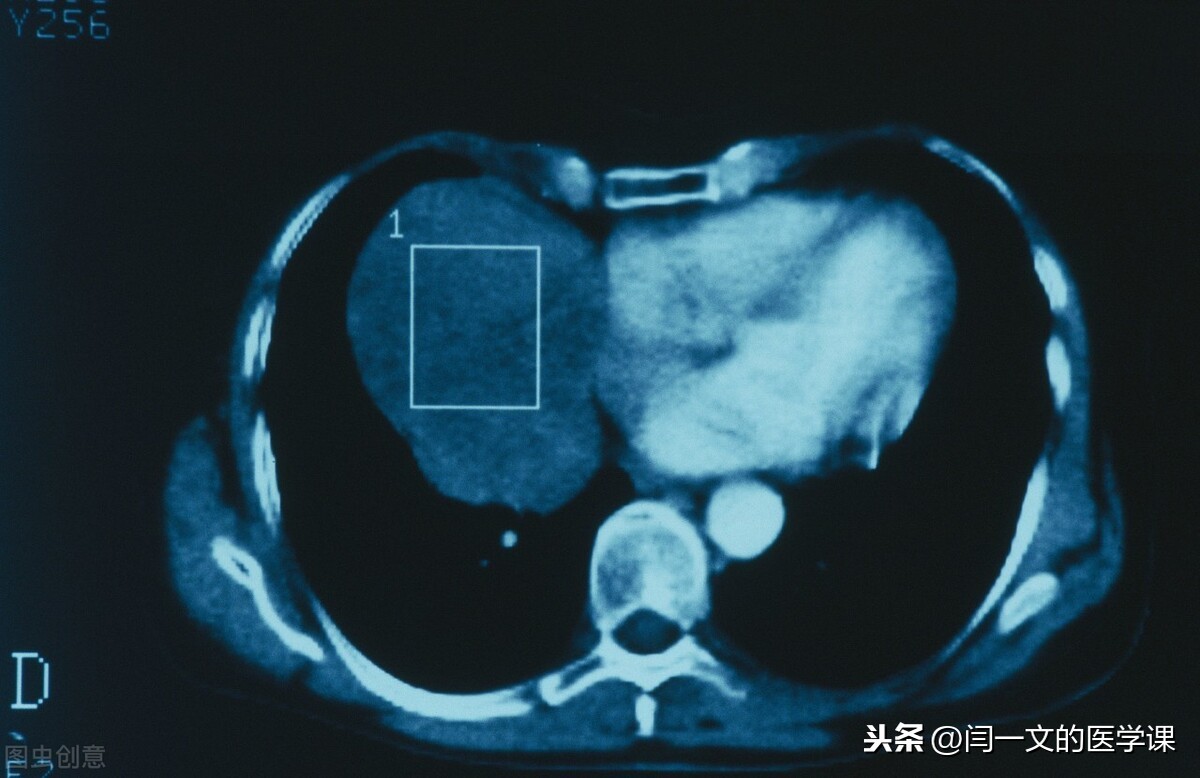

(2)恶性肿瘤:生长快,侵袭性生长(器官侧象树根一样向器官浸润)或外生性生长(突出器官外或粘膜表面生长);摸之一般不能移动(浸润性生长缘故),与周围边界不清,可以发生转移;治疗后易复发;全身症状明显:如低热、消瘦、贫血等,如不及时治疗,常导致死亡。

癌是指来源于上皮组织的恶性肿瘤,上皮组织包括被覆上皮、腺上皮及感觉上皮。如肺的鳞癌(被覆上皮来源)、腺癌(腺上皮来源)。

肉瘤是指间叶组织来源的恶性肿瘤,间叶组织包括纤维结缔组织、脂肪、肌肉、脉管、骨和软骨组织等,如骨肉瘤、脂肪肉瘤等都属于间叶组织来源恶性肿瘤。若医生说某人患的是胃癌,意思是患者的胃黏膜上皮形成的癌(上皮来源);若说患者得的是胃肉瘤,则表明这种恶性肿瘤不是由黏膜上皮细胞所形成的,可能由平滑肌细胞(属于间叶组织)恶变引起。